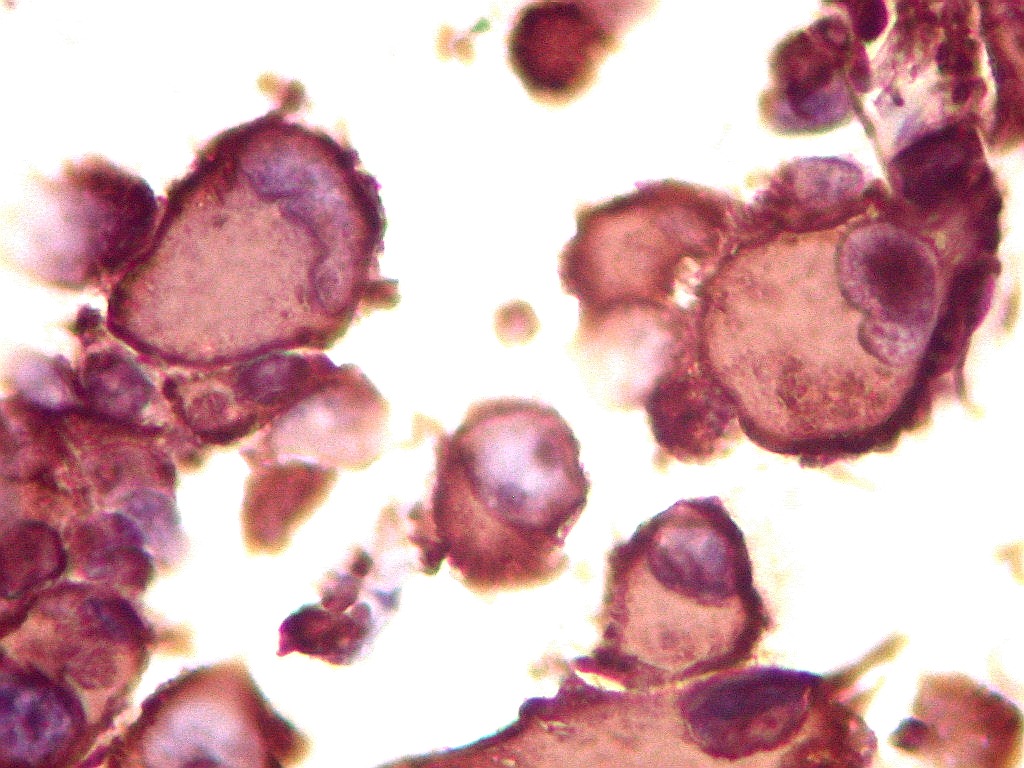

Tumor teratóide rabdóide atípico de III ventrículo.

Vimentina.   Filamento intermediário ubiquitário, presente em tecidos de várias linhagens. Aqui expressada nas células tumorais e no tecido nervoso, inclusive em células ependimárias.